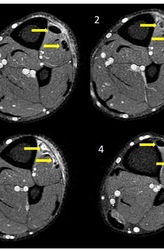

• Положительный клинический тест Финкельштейна — боль в тыльно-лучевом отделе запястья при локтевом отклонении запястья с кулаком, сомкнутым над согнутым большим пальцем (черная стрелка).

Результаты рентгенографии — на фоне локальной остеопении шиловидного отростка лучевой кости слабо выраженное прилегание надкостницы (белая стрелка) и отек мягких тканей (желтая стрелка).